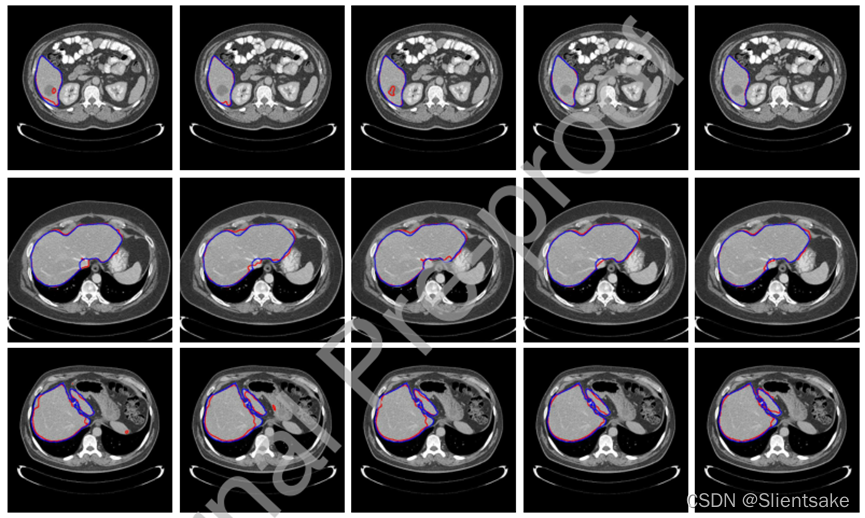

在图5中展示了训练比为5%的LiTS数据集上的定性分割结果,CFCN和C2FCN在划定病理肝脏分割的边界和保持类内一致性方面优于对比方法,结果表明,所提出的方法仅在较小的训练集上就能有效地对目标对象流形进行建模,并消除类内不一致的影响。

图5所示:在LiTS数据集上训练比例为5%的分割结果示例。这里,蓝色和红色线分别表示deep模型的ground truth和自动分割结果。